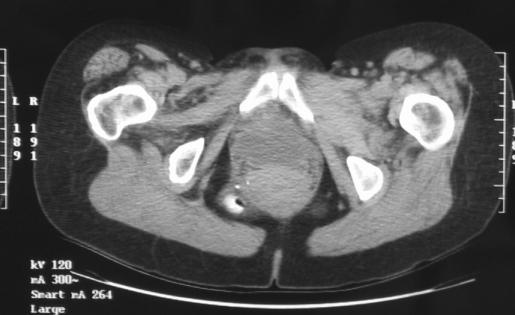

Perineal hernia is a rare but known complication following major pelvic surgery. It may occur spontaneously or following abdominoperineal resection, sacrectomy, or pelvic exenteration. Very little is known about spontaneous perineal hernia. Surgical repair via open transabdominal and transperineal approaches has been previously described. We report laparoscopic repair of spontaneous and postoperative perineal hernia in 2 patients.

会阴疝是盆腔大手术后一种罕见但已知的并发症。它可能自发出现,也可能在腹会阴联合切除术、骶骨切除术或盆腔脏器清除术后发生。关于自发性会阴疝,人们了解甚少。以往已有经腹开放和经会阴入路进行手术修复的报道。我们报告了2例自发性和术后会阴疝的腹腔镜修复病例。